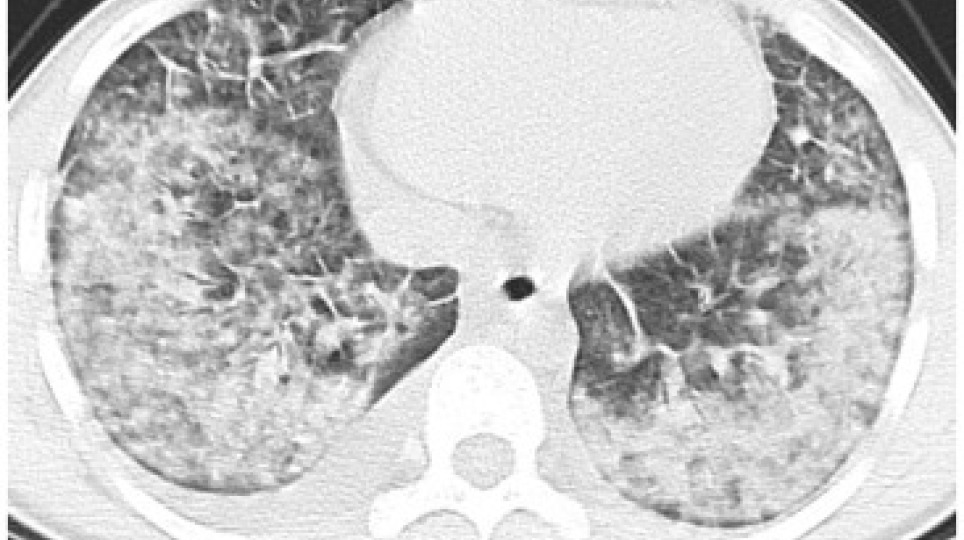

使用電子煙,肺病風險可能提高4-5倍!

2020/12/28